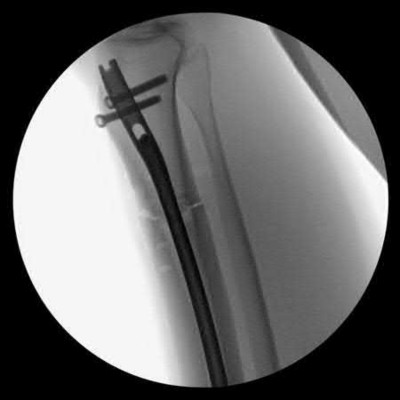

Question 38:

In the treatment of unstable intertrochanteric femur fractures with a cephalomedullary nail, achieving correct lag screw placement is critical. According to the original study by Baumgaertner et al., what is the ideal tip-apex distance (TAD) recommended to minimize the risk of lag screw cut-out?

Options:

- Less than 10 mm

- Less than 15 mm

- Less than 25 mm

- Less than 35 mm

- Greater than 25 mm

Correct Answer: Less than 25 mm

Explanation:

Baumgaertner et al. defined the tip-apex distance (TAD) as the sum of the distance from the tip of the lag screw to the apex of the femoral head on both AP and lateral radiographs, after correcting for magnification. A TAD of less than 25 mm was shown to significantly correlate with a minimal risk of lag screw cut-out in the treatment of intertrochanteric fractures.